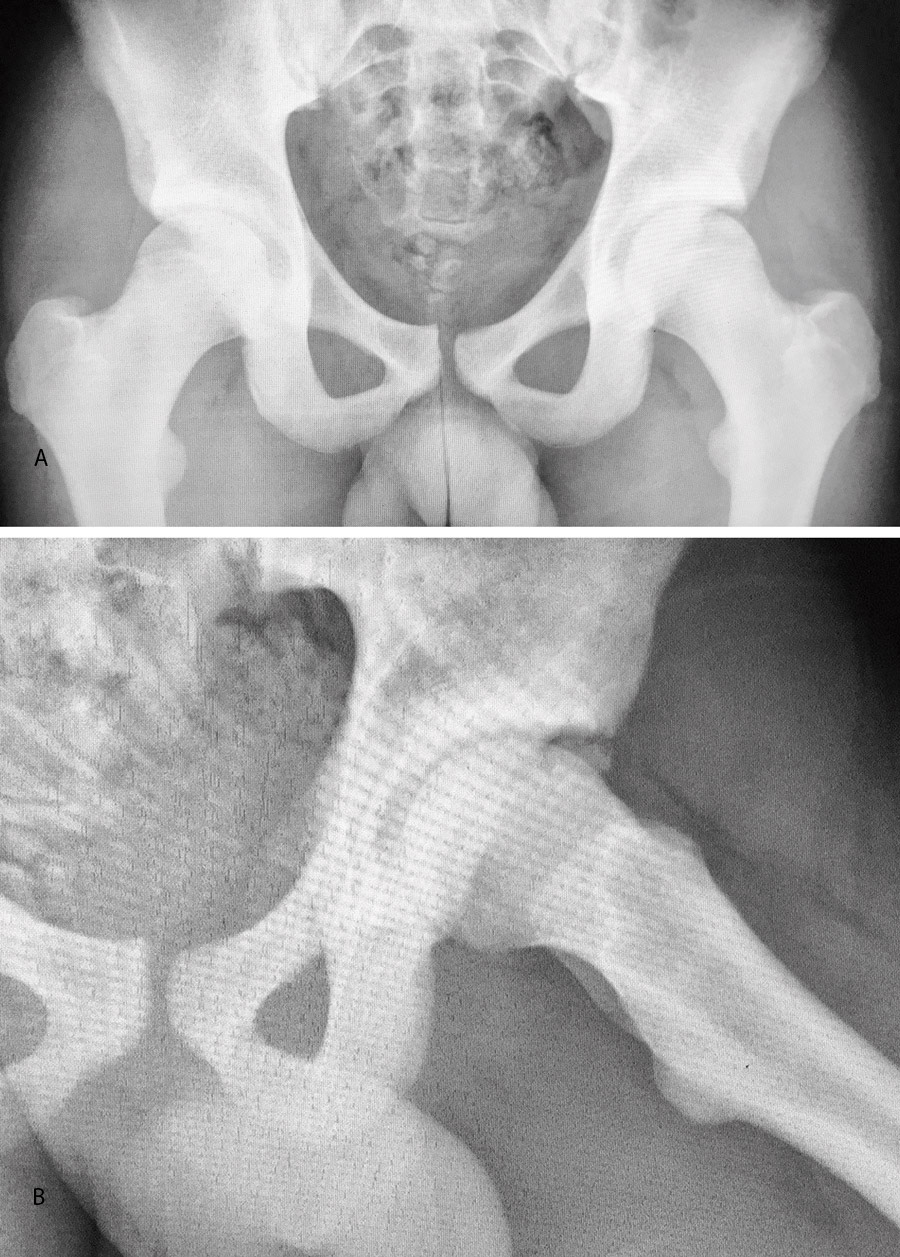

El estudio de imagen mostraba una ausencia de deformidad ósea y no se apreciaron lesiones en la radiografía ni la artrorresonancia (Figuras 1 y 2). El ángulo alfa en la imagen axial izquierda era de 49,6°, mientras que el ángulo de cobertura acetabular de Wiberg era de 34,6°.

Las pruebas de imagen no muestran alteraciones en forma de deformidad de tipo CAM ni PINCER (tanto en radiografías como en resonancia). El ángulo alfa en la proyección axial era de 38,2° y el ángulo Wiberg de 34,5° (Figura 5). Asimismo, el estudio mediante artrorresonancia no evidenció lesiones de labrum ni deformidades del tipo AFA (Figura 6).